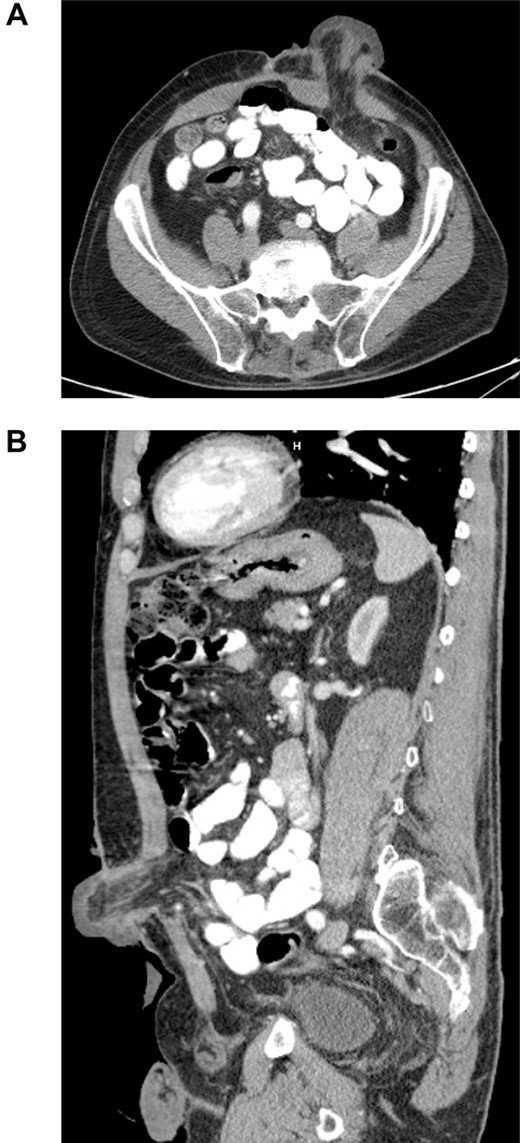

The patient is a 72-year-old male with a significant surgical history of an exploratory laparotomy with rectosigmoidectomy and end colostomy for a perforated stercoral ulcer 4 months prior to presentation. The patient was evaluated for colostomy reversal and underwent colonoscopic evaluation to assess the rectal stump and the remaining colon. The 10-cm rectal stump was found to have no abnormalities. The left lower quadrant colostomy was intubated, and the scope was advanced to the cecum and then carefully withdraw with circumferential evaluation of the mucosa. No polyps or abnormalities were identified. The patient tolerated the procedure well without any immediate complications and was discharged with planned colostomy reversal in the near future. The patient presented to the emergency department 1 week after the colonoscopy with a 1-day history of swelling and tenderness of the stoma with diminished output. On physical examination, there was no evidence of peritonitis, however, the stoma was edematous with evidence of ischemia (Fig. 1). Computed tomography (CT) of the abdomen and pelvis demonstrated edema of the stoma above the level of the fascia (Fig. 2). The patient was initially managed non-operatively without improvement and then the decision was made to take the patient to the operating room for colostomy reversal. A circumferential incision around the edematous stoma was made and this was dissected free from the subcutaneous and fascial attachments, which were minimal. The segment of stoma above the skin was ischemic, and upon mobilization of the colostomy, a colocolonic intussusception of the proximal colon into the colostomy was encountered. The intussusception was carefully reduced and the colon proximal to this area appeared to be well perfused, pink and viable. Following this, an exploratory laparotomy was performed and a standard stapled coloproctostomy was created. To protect the low anastomosis, a diverting loop ileostomy was created. The patient had an unremarkable post-operative course and was discharged from the hospital on post-operative day 3.

Axial (A) and sagittal (B) CT of the abdomen and pelvis, with IV contrast demonstrating edematous colostomy above the level of the fascia.